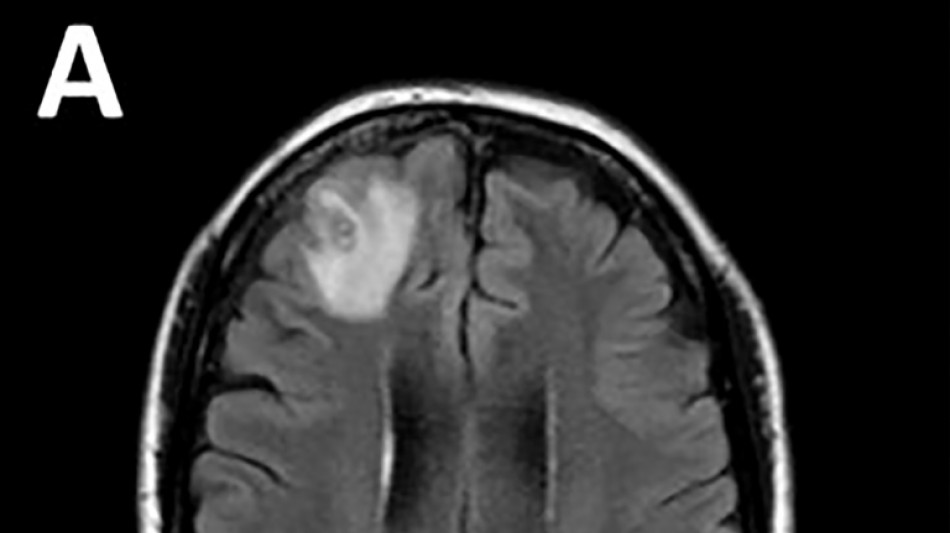

Un ver qui parasite les serpents découvert dans le cerveau d'une Australienne / Photo: Handout - Université nationale australienne/AFP

Les médecins ont découvert une "lésion atypique", grâce à un examen IRM, dans la partie frontale du cerveau de l'Australienne, âgée de 64 ans, qui souffrait de pertes de mémoire.

Le parasite, dont la "structure en forme de fil" est apparue sur les scanners cérébraux, a ensuite été identifié grâce à des tests ADN.